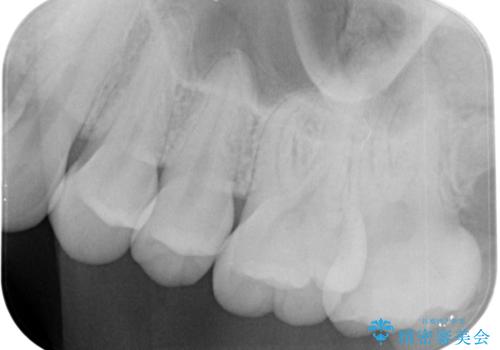

奥歯の黒いのが気になる。

- 奥歯が黒いとの事で来院。

歯の表面がう蝕になっていたので拡大鏡でう蝕を除去し、e-maxインレー(セラミックインレー)で治療を行いました。